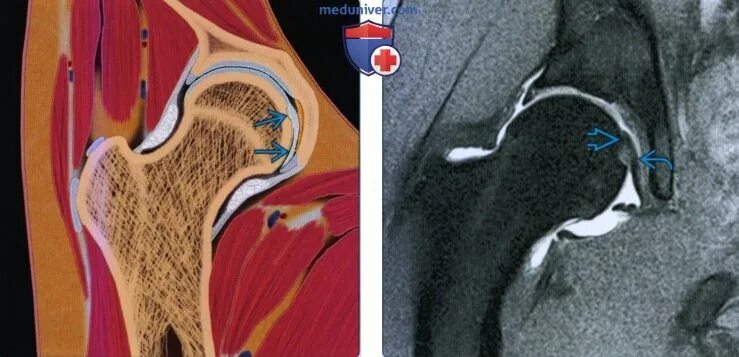

Повреждение связок тазобедренного сустава